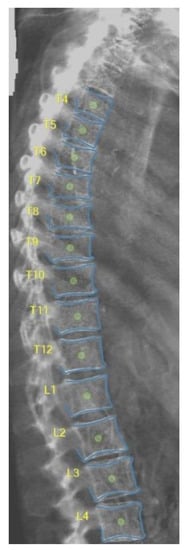

2.3. DXA-VFA Image Annotation

3.1. Vertebral Level Assignment

3.2. Point-Wise Landmark Annotation Accuracy

3.3. Image-Wise Annotation Accuracy